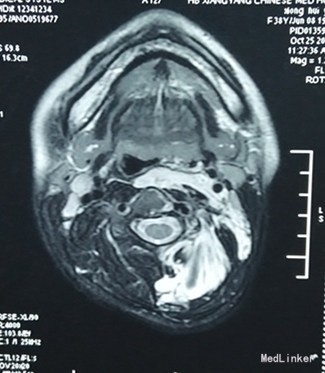

患者,女性,38岁“左侧头部闷痛伴左上肢麻木4天”入院。现病史:患者自诉于4天前无明显诱因出现左侧头部闷痛,伴左上肢麻木,左侧肩背部疼痛剧烈,左眼胀痛、耳鸣不适,无发热盗汗,无咳嗽咳痰,无头晕,无视物旋转等不适。当地医院颈部MRI报:1、颈部、咽后壁、左(L)胸部、纵膈内软组织大面积异常信号伴软组织肿块及骨质侵蚀,考虑恶性病变,2、双侧颈静脉链淋巴结增大,左(L)锁骨上淋巴结融合成团,3、颈椎曲度变直,键盘变性、膨隆。我院按“颈部包块”收治入院

查体:左侧颈部皮下饱满,触之稍韧,腹软无压痛,站立时左侧肩背部及左侧上腹部可扪及多个皮下包块,质软,无明显压痛,大小不一,大者约6*7cm,小者2*3cm,余无异常。 我院胸部CT: 1、左颈部、左背部及纵隔见大片软组织影,增强呈不均匀大小不等结片状强化,强化程度与血管强化程度相似,向上累及左咽旁间隙、左咽后间隙、左侧椎旁、椎后软组织,向前累及胸锁乳突肌后缘、左锁骨上,侵犯纵隔,以上纵隔为主,向后延伸椎旁、背部软组织及皮下脂肪间隙呈多发结节影,左侧胸膜呈多发结节影,向下侵犯左侧腹膜及左肾上极,呈多发大小不等软组织密度结节样改变,其内少许钙化影,所及多椎体及左侧肋骨多发骨质破坏;上述弥漫性病灶考虑肿瘤性病变,不除外血管瘤可能。 我院腹部CT: 1、左肾上区、脾周、腹膜后、左肾前、左侧腹腔及腹膜下多发团片状软组织密度影,散在多发钙化灶,左肾前肿块似与左肾静脉相通,左肾前肿块延左侧腰大肌前外侧向下延伸至盆腔左侧,左侧腹腔及腹膜下肿块向外播散至腹壁,腹直肌、腹外肌受侵,考虑肿瘤性病变,血管瘤不除外,建议进一步检查; 2.肝内多发低密度结节影,增强扫描呈渐进性强化,不除外血管瘤可能,建议必要时MR检查。

为求进一步诊断,来我科室之后行腹腔镜探查术和腹壁取活检术。确诊为多发性血管瘤。 侵及左侧咽喉部,左颈部、左背部及纵隔,左肾上区、脾周、腹膜后、左肾前、左侧腹腔及左侧腹壁